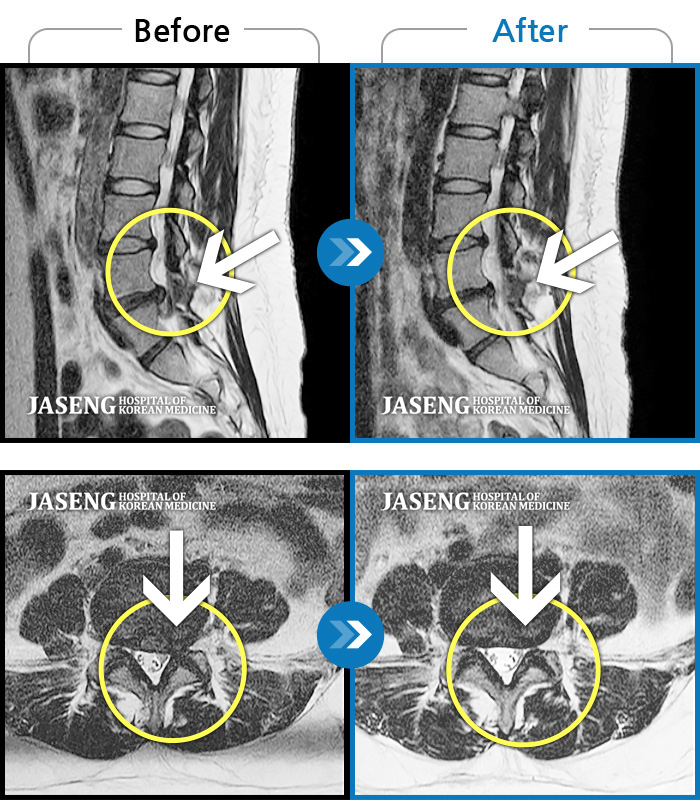

Before

After

환자에게 사전 동의를 받아 동일 조건에서 촬영되었습니다.

개인에 따라 치료 후 부작용이 발생할 수 있으니 의료진과 상담 후 치료를 진행하시기 바랍니다.

허리통증과 좌측 하지방사통